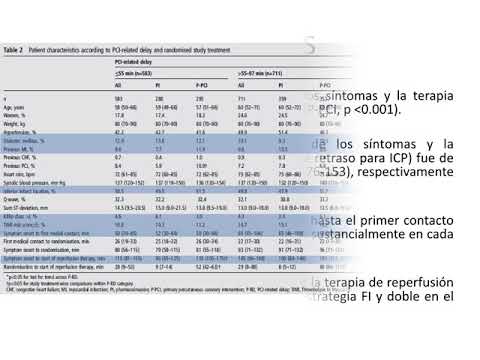

Estrategias fármaco invasiva para ATC primaria. Dr. Juan Pablo Lestard. Residencia de Cardiología. Hospital C. Argerich. Buenos Aires